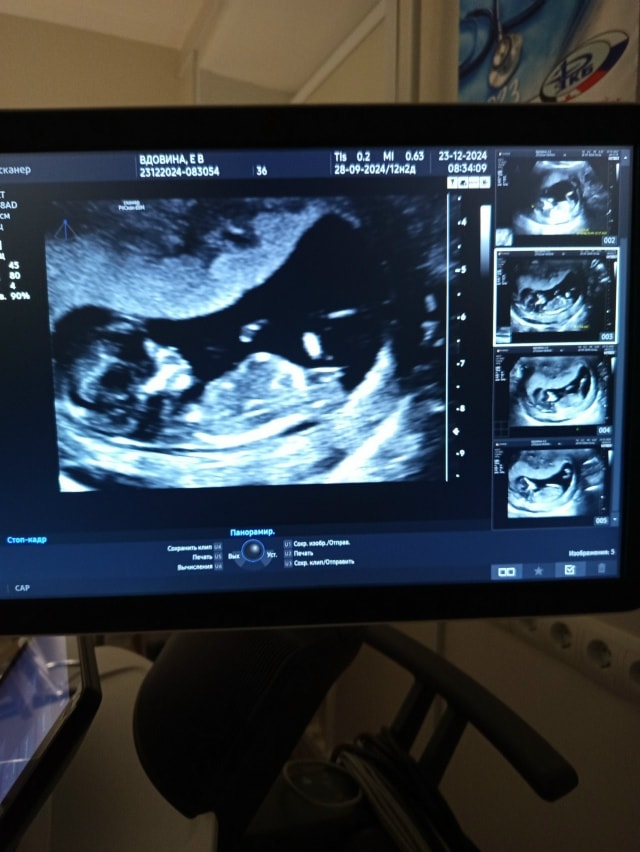

Страхи, переживания и немножечко нытьяСрок по месячным 8,3.

ПЯ отстаёт по сроку на 6 дней. ПЯ 25 мм (срок 7,4). Эмбрион ктр 21 мм, срок по УЗИ 8,5 недель. Врач сказала, что это нормально, такое бывает. А я вот переживаю, не задавит ли ПЯ эмбрион?

По фото ПЯ как будто сплющено.

А с виду и не скажешь что пя маленькое. Малыш свободно плавает... У меня примерно также выглядела в 8 недель

Наталья, сейчас скину. Тут КТР 2.2 см. Срок 8.6. Плодное 4.3 см.

Джеллибин, ну по размером примерно одинаково. Небольшая разница. Надеюсь, что неправильно измерили, потому что по 3д снимку там много места. Ну посмотрим, записалась на вторник на УЗИ ещё.